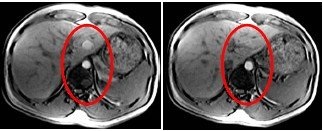

Use CCOMP for breath-hold abdominal images to reduce pulsatile flow artifact. Without CCOMP, pulsatile flow artifact from the aorta is very noticeable.